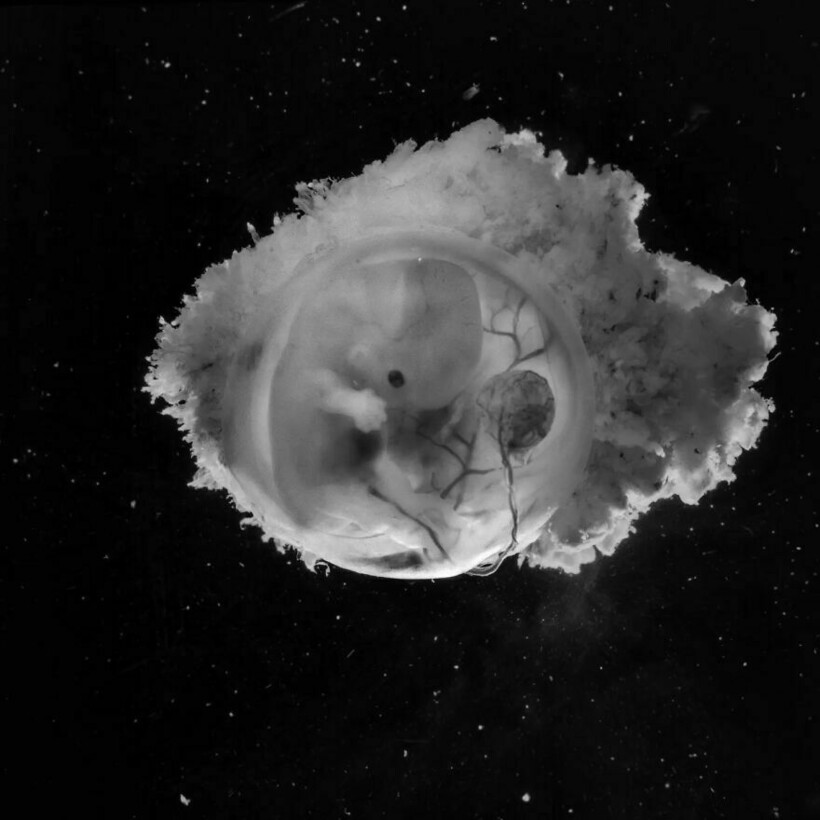

Леннарт Нильссон стал настоящей легендой фотографии, ведь он сделал то, чего не удавалось никому: показал миру, как развивается ребенок в утробе матери. Его проект «Ребенок родился» был создан в 1960-х годах, и он представляет собой детальные снимки эмбрионов на разных стадиях развития. Фотографии стали сенсационными, впервые они появились в журнале LIFE, и одна из них украсила обложку. На протяжении многих лет эти снимки публиковали в разных журналах.

Однако Леннарт с середины ХХ века увлекался микроскопией

А позже он экспериментировал с новыми методами фотографирования

Фотограф снимал детей в утробе матерей во время медицинских процедур

Он присутствовал на амниоцентезе и лапароскопии

Нильссон не скрывал, что снимал и эмбрионы после выкидышей и абортов

Почти все эти снимки сделаны в 1965 году, однако Нильссон фотографировал до конца своей жизни, и запечатлел не только развитие эмбриона, но и само зарождение жизни: вот тут мы собрали другие его фотографии.